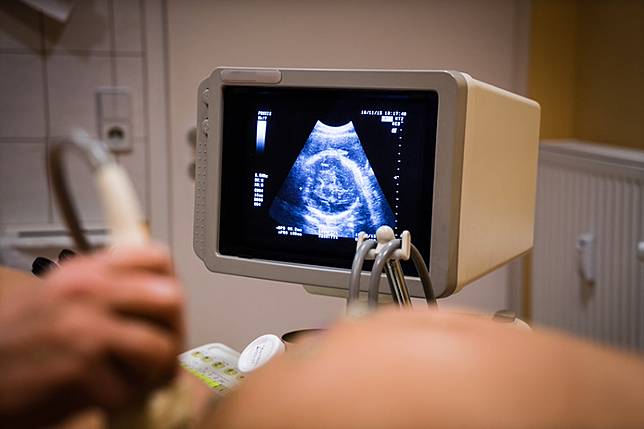

高層次超音波的最佳檢查時間建議是在懷孕21至23週之間,這段時間較適合進行詳細的結構檢查。原因包括:

此外,有些醫療機構建議的時間範圍稍微寬鬆,約在20至24週之間進行高層次超音波檢查,能夠全面評估胎兒的腦部、心臟、內臟、四肢等結構,並同時檢查子宮頸長度、臍帶血流等,整體檢查時間約30至60分鐘。